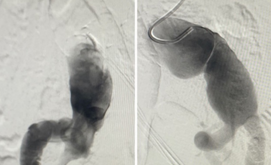

The Abdominal Aortic Aneurysm (AAA) was extending from the infra-renal aorta to both Common iliac arteries. Endovascular Aneurysm Repair (EVAR) was planned. Generally, an EVAR is done by surgically exposing femoral arteries bilaterally to take the grafts inside the aorta for Endovascular repair. We did the EVAR completely percutaneous- avoiding any surgical exposure. No Groin Cut, No surgical femoral artery exposure # SIMPLY Percutaneous. The patient Got discharged in 48 Hrs. It’s actually technically challenging to create 2 X two sets of pre-close sutures / Bilateral femoral for 20F (6mm) holes on Common femoral arteries. The procedure was done with suture closure of Bilateral 6 mm holes over the femoral without exposing the femoral - that’s the beauty.

suture-less-endovascular-aneurysm-repair-for-abdominal-aortic-aneurysm-4